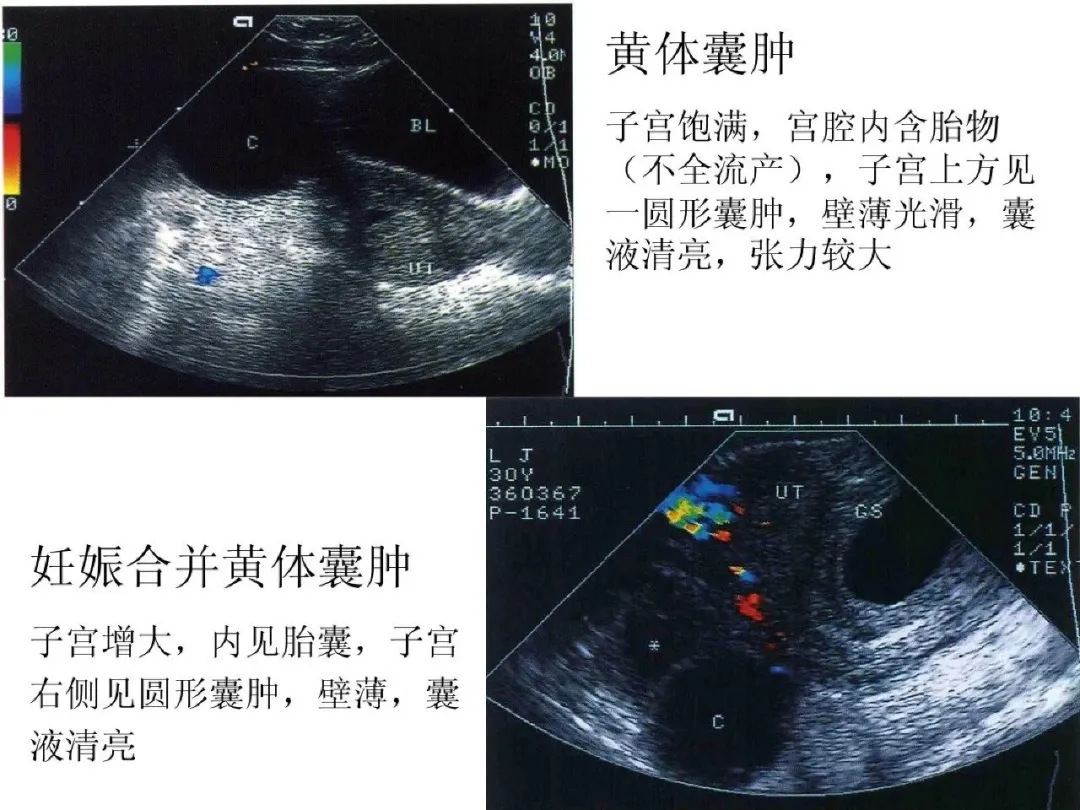

卵巢非赘生性囊肿

●卵泡囊肿(成熟卵泡未破裂):多呈圆形;大小多为2-3cm,囊壁薄而光滑;囊液清亮;囊肿多位于子宫一侧或侧后方,多为单侧。

●黄体囊肿(多见于子宫内膜分泌期或妊娠早期):大小多为2-3cm或更大;个别黄体囊肿可破裂出血而出现急腹症。

●黄素囊肿:囊肿较大;呈不规则形、叶状;内部可有分隔,呈车轮状;壁薄而光滑;隔壁上可显示血流信号。